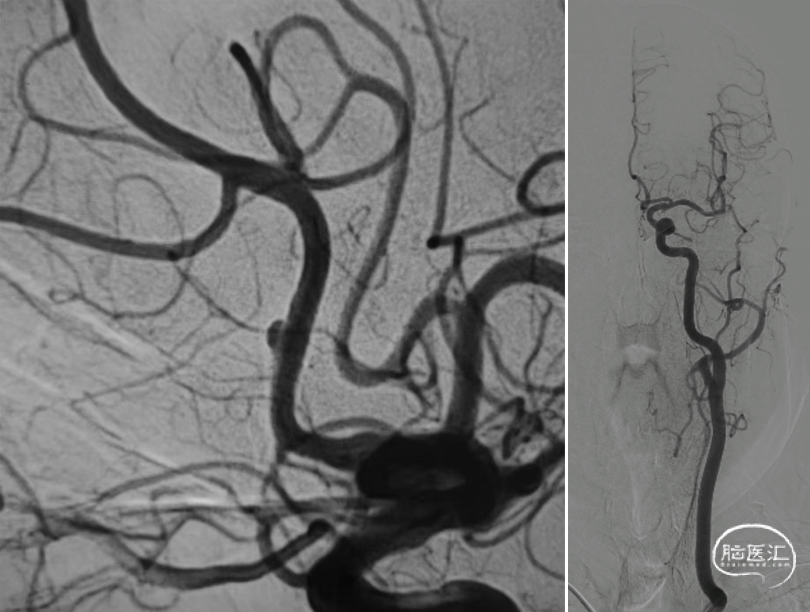

锁骨下动脉扭曲,III型弓。

右侧颈动脉造影:海绵窦、眼段动脉瘤。

左侧颈内动脉造影:颈内动脉起始部中度狭窄,海绵窦段、床突上段多发动脉瘤。

跨弓角度大,可见赛诺神畅 6F-105 APEX TRA®经桡远端通路导引导管柔软段跨越转弯处后沿泥鳅导丝一次顺利到达岩骨段。

导管顺利到位。